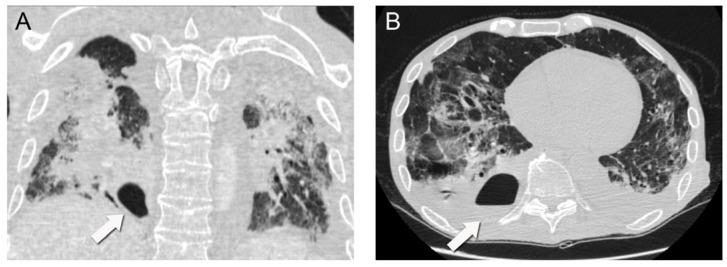

Intraparenchymal lung abscess development associated with severe acute respiratory syndrome coronavirus 2 (SARS-CoV-2) infection is a rare complication, with only half a dozen primary cases having been reported in the literature. We present the case of a patient with Waldenström's macroglobulinemia who developed a lung abscess subsequent to a primary SARS-CoV-2 infection. We present a 63-year-old male patient with SARS-CoV-2 infection and a history of Waldenström's macroglobulinemia who developed a cavitating intraparenchymal lung abscess with an air-fluid level in his right lower lobe two weeks following admission to hospital. The patient became septic and developed acute respiratory failure requiring mechanical ventilation and intensive care. He was managed with broad-spectrum antibiotic therapy and aspiration drainage, but unfortunately due to his severe clinical condition died 20 days after his initial admission. The development of a lung abscess in patients with COVID-19, although rare, can be quite compromising and even prove fatal, especially in immunocompromised patients. Clinicians should be aware of this potential complication.

与严重急性呼吸综合征冠状病毒2(SARS-CoV-2)感染相关的肺实质内肺脓肿是一种罕见的并发症,文献中仅报道了少数几例原发性病例。我们报告了一例患有华氏巨球蛋白血症的患者,该患者在原发性SARS-CoV-2感染后发生了肺脓肿。我们介绍了一名63岁男性患者,他感染了SARS-CoV-2且有华氏巨球蛋白血症病史,入院两周后右下叶出现了一个有气液平面的空洞性肺实质内肺脓肿。患者发生败血症并发展为急性呼吸衰竭,需要机械通气和重症监护。他接受了广谱抗生素治疗和穿刺引流,但不幸的是,由于他的病情严重,在初次入院20天后死亡。COVID-19患者发生肺脓肿,虽然罕见,但可能极具危害性,甚至可能致命,尤其是在免疫功能低下的患者中。临床医生应意识到这种潜在并发症。